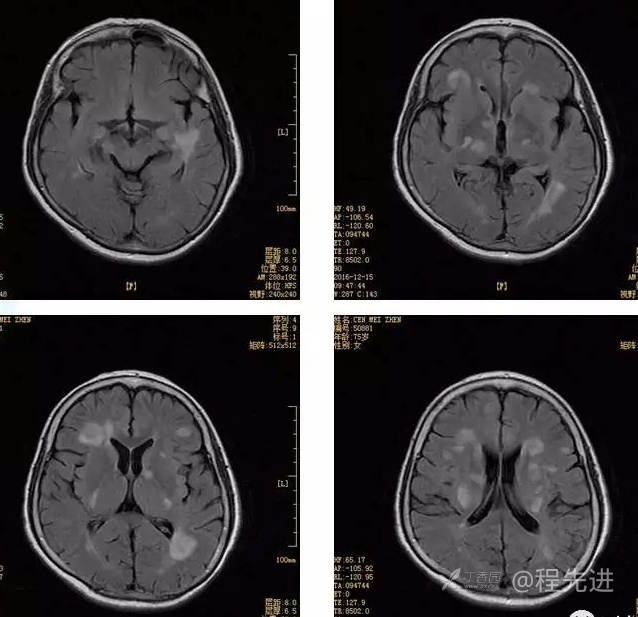

3月特别精彩病例|头晕伴左侧肢体乏力、行走不稳1周【结果已公布】

患者性别:女

患者年龄:75岁

简要病史:头晕伴左侧肢体乏力、行走不稳1周。否认高血压、脑梗塞、肝炎、糖尿病、肺结核病史。否认疫区疫水接触史。